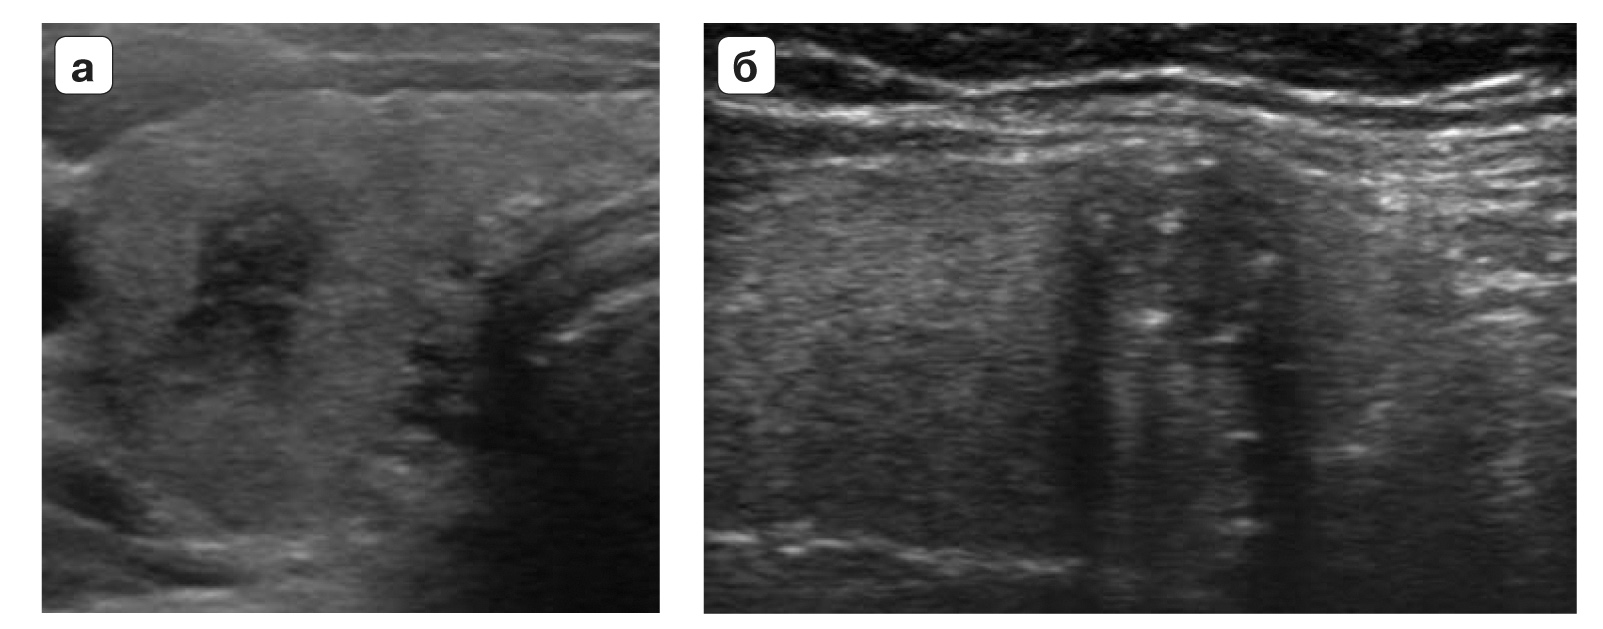

TI-RADS 2. Очаговые образования, не требующие морфологической оценки (макрофолликулы; губчатые или кистозные узлы), представленные на рис. 1.

Рис. 1. Категория TI-RADS 2: а – кистозно расширенный или макрофолликул; б – губчатый узел (стрелки).